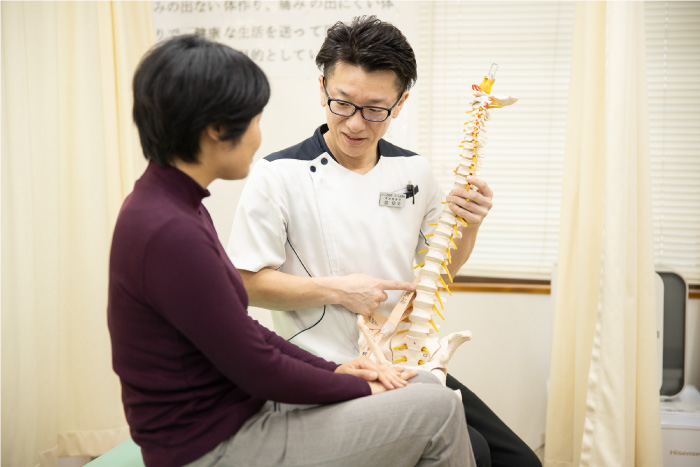

初めての方には、姿勢のチェックと過去の痛みなどをしっかり聞き取り今回の原因と今後の再発防止のために体の使い方から原因の特定をします。(約30分前後)

痛めた場所を目でみて触って、なぜそこが痛くなるのか分かりやすく説明します。

分かりにくい説明には、骨の模型や絵を書くことで誰が聞いても理解出来る様に心掛けています。必ず理解いただけますのでご安心下さい。

(分からない場合は、何回でも説明しますので安心ください。)